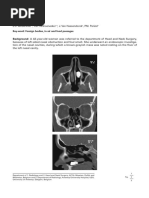

Coronal CT Image showing rhinolith between the right

inferior turbinate and the septum. In addition, the patient

has bilateral sinusitis and a septal deviation.